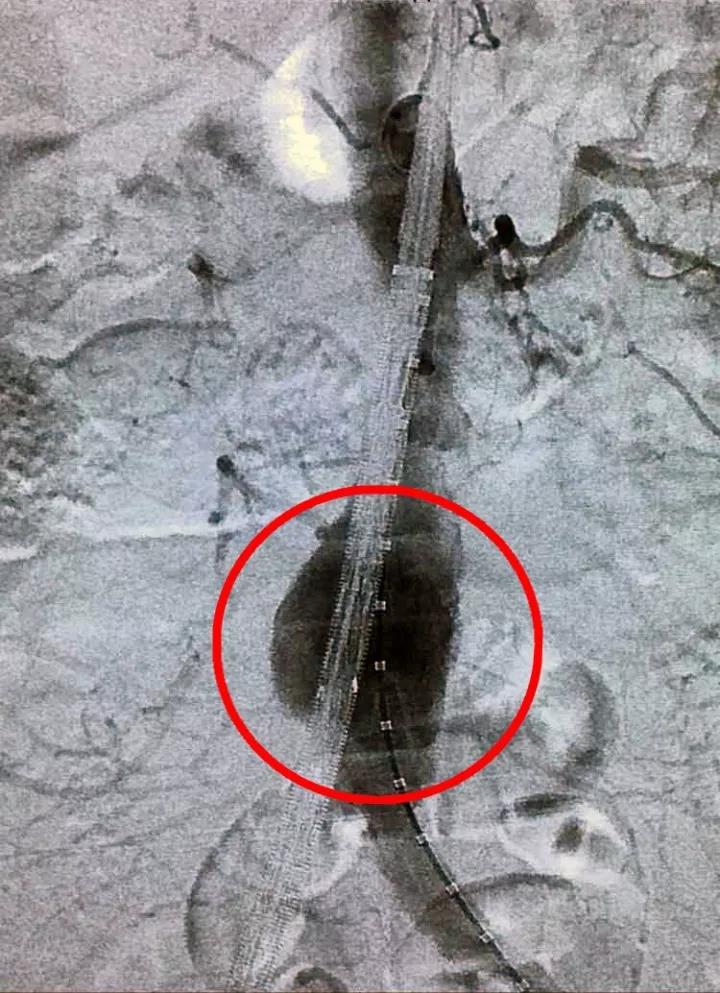

12月6日,患者被送入介入手術(shù)室,醫(yī)護(hù)人員同時(shí)以最快速度做好術(shù)前準(zhǔn)備。介入室中,手術(shù)團(tuán)隊(duì)根據(jù)DSA造影再次明確診斷及病變的手術(shù)指征,迅速對(duì)瘤體做出評(píng)估與測(cè)量,討論并確定了腹主動(dòng)脈瘤覆膜支架植入腔內(nèi)隔絕術(shù)的詳細(xì)手術(shù)方案。手術(shù)團(tuán)隊(duì)經(jīng)患者大腿股動(dòng)脈植入覆膜支架,將動(dòng)脈瘤腔隔絕后重建新的腹主動(dòng)脈腔血流通道。原動(dòng)脈瘤腔因無(wú)血流沖擊,瘤壁壓力得到解除,從而避免了瘤體的破裂。

手術(shù)前